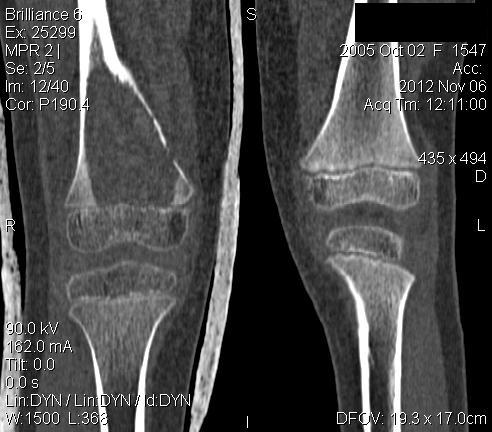

3 месяца назад в отделении была прооперирована девочка 7 лет с клинико- рентгенологической картиной аневризмальной кисты (открытая биопсия).

Гистологическое заключение местных гистологов и ФНКЦ им. Д. Рогачева -аневризмальная киста. 2 недели назад девочка взята на костную пластику - на операции полный лизис костной ткани циркулярно на протяжении 10 см от эпифиза на 10 проксимальней и массивное артериовенозное крововтечение из оставшейся надкостницы . Операция закончена наложением стержневого аппарата и остановкой кровотечения тахокомбом, тампонадой мышцами. Повторная гистология неоднозначна. ФНКЦ им. Д. Рогачева дает прежний результат , ФГБУ РОНЦ НН Блохина -телеангиэктатическая остеосаркома, онкологи из института Герцена - киста .Как быть дальше. Кому верить и что делать? Заранее благодарен.